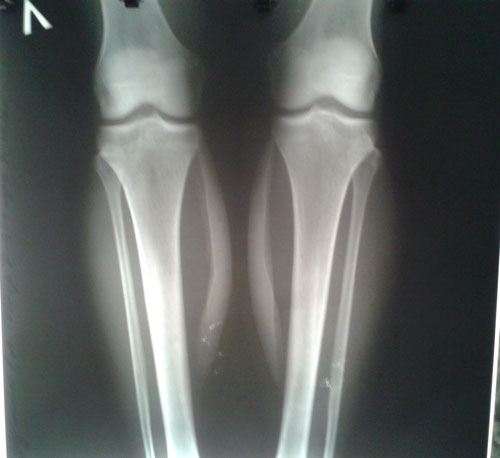

Исходник - 28 лет.

Дата операции 31.08.2016г.

У пациентки круропластика. Ситуация не ординарная, т.к. исправляем не деформацию, а внутреннюю ротацию (двойную) 45 градусов. Из за неё, у девочки после нагрузки - боли в ногах и при ходьбе - стопы бросает во внутрь.